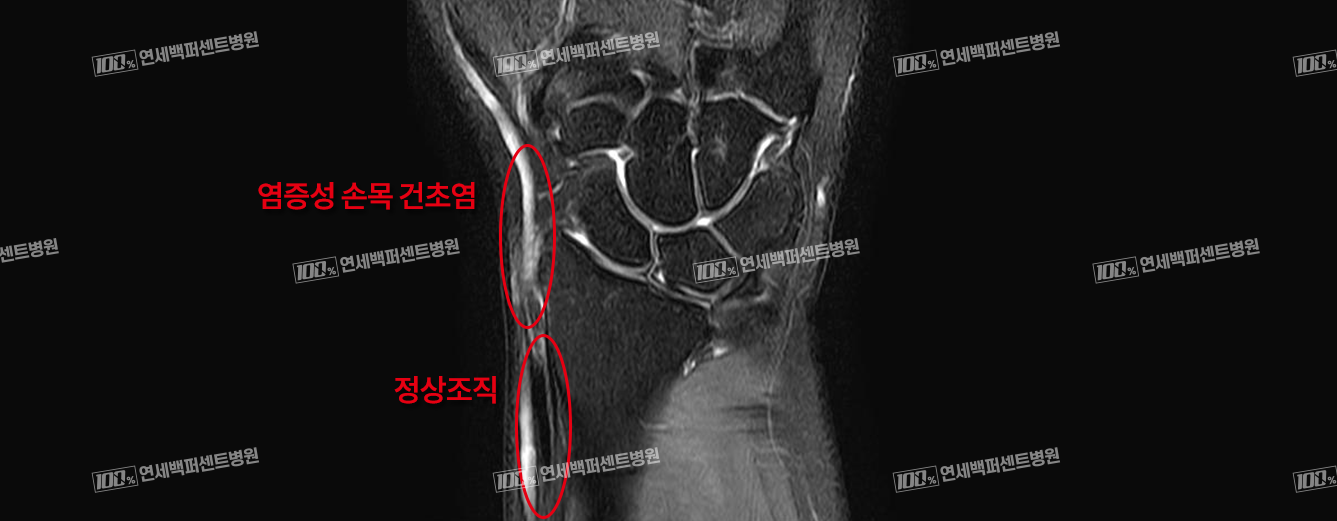

손목건초염 MRI 사진

연세백퍼센트병원의

손목건초염은 손목을 지나는 힘줄(건)을 감싸고 있는 막(건초)에 생긴 염증을 말합니다.

손을 과도하게 사용하면 힘줄 주변에 염증이 생기고 통증을 일으키게 됩니다.